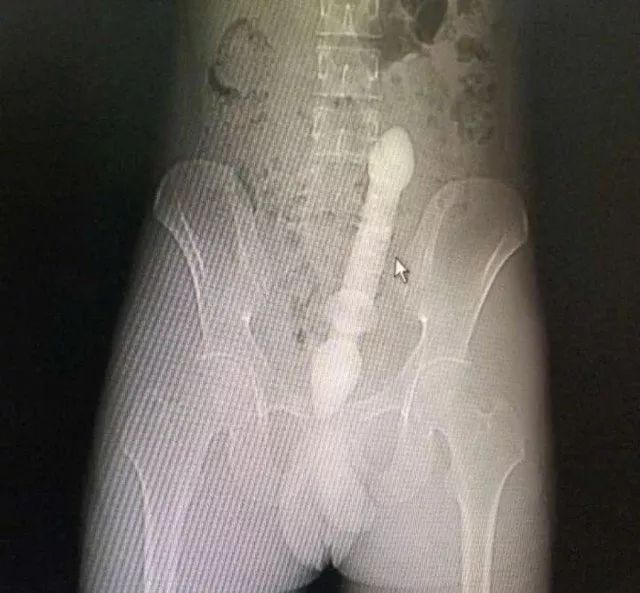

CT三维重建下三条泥鳅的骨骼清晰可见

2月10日那天我看的急诊,事情的经过是这样的,我是他的首诊大夫,一开始急诊打电话急会诊说是吃泥鳅吃坏了肚子,我觉得这也没啥,然后让他做腹部CT。后来看到他的CT赫然三条鱼骨头。我一看CT很吃惊,难道是生吃的?

去一楼急诊问患者本人,当时我听他说了事实,是下面塞进去的真把我吓一跳。他第一句话就是说,听信网上前列腺偏方把他害惨了,让我救救他赶紧手术,问我有没有穿孔,当时只有一个小时,还早,摸着板状腹很硬。他意识还有,后来就慢慢感染中毒休克了。后来术中发现乙状结肠穿孔,三条鱼都到了腹腔里,有一条还往回盲部钻,不过取出来应该都是死的了。